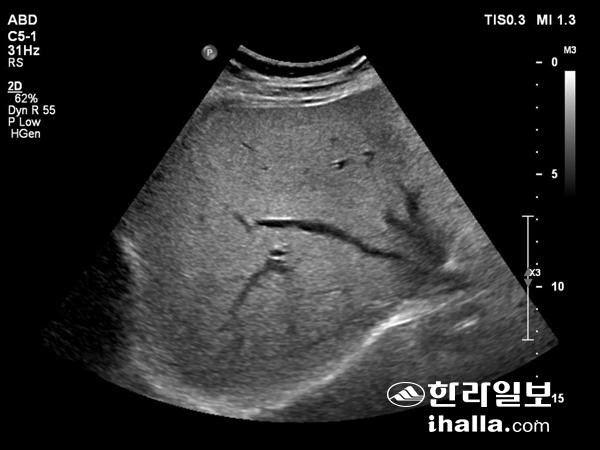

신장 초음파.

초음파 영상을 실시간으로 보면서 간종양, 간실질, 췌장종양 등에 대해 조직검사를 할 수도 있고, 초음파 유도 하에 작은 간암에 대해 고주파열치료 같은 치료를 시행할 수도 있다. 비뇨기계 초음파의 경우 혈뇨, 옆구리 통증, 신기능 이상 등에 대한 원인 감별을 위해 시행하고, 신낭종이나 신결석 등의 추적 관찰에도 이용한다. 우하복부 통증의 경우 응급수술을 요하는 질환인 충수돌기염을 배제하기 위해 충수돌기 초음파를 시행하고, 하복부 통증 역시 소장 및 대장 초음파를 통해 원인을 찾아 볼 수 있다.

대부분의 복부 초음파검사는 환자가 천정을 보고 똑바로 누워있는 상태에서 시작하고 검사 중에 옆으로 돌아 눕거나 반쯤 일어나 앉을 수도 있다. 신장 초음파의 경우 몸의 뒤쪽에 위치하는 장기 특성상 시작부터 옆을 누워 시행할 수 있다. 탐촉자와 신체에 초음파 젤리를 바른 후에 검사를 시작한다. 이 젤리는 탐촉자와 피부 사이의 공기를 제거해 탐촉자와 피부가 밀착되게 하고 잘 미끄러지게 하는 필수적인 역할을 한다. 젤리는 인체에 전혀 무해하고, 대부분의 경우 옷에 묻어도 쉽게 세탁된다. 그 다음 검사자가 탐촉자를 눌러 피부와 완전히 밀착시킨 검사 부위를 문지르면서 검사를 시행하게 된다. 상복부 장기들이 잘 보이게 하기 위해 검사자가 숨을 크게 들여 마시거나 배를 불리도록 요구하게 되는데, 이렇게 하면 횡격막이 아래로 내려오기 때문에 횡격막 아래에 있는 간이 늑골 아래로 내려 와서 간이 잘 보이기 때문이다.